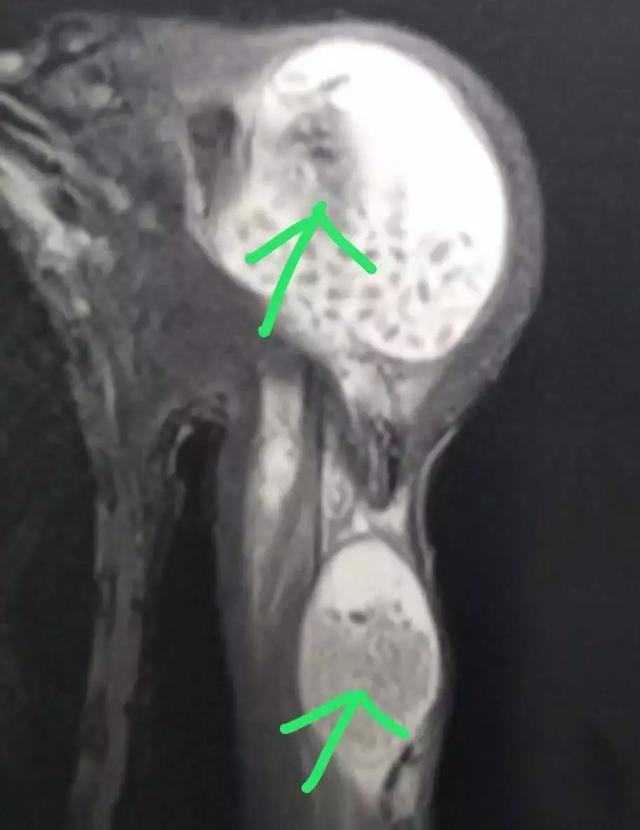

一个多月前,40来岁的赵哥(化名)发现自己的左肩关节肿起来了,肩部无力,抬不起来,并伴随有疼痛感,怀疑是肩关节炎,吃了药后一直没有好转,来到湘雅医院骨科就诊后,通过核磁共振影像,发现赵哥的左肩关节里面布满了一粒粒的“米粒”样的颗粒。

核磁共振影像图

手术进行了1个多小时,清除出来的颗粒物有一盆,数量多达上百颗,这些跟米粒大小的颗粒物,质软,实心,据了解,这种米粒体于1895年由Riese在关节结核中首次描述,目前对其形成过程仍存在争议,可能是滑膜炎症、增生以及蜕变的产物,这些脱落的滑膜在滑液里被纤维蛋白包裹形成了米粒体,或者是在滑液中独立合成。米粒体由纤维蛋白、网状蛋白及胶原等组成。其诊断主要依靠核磁共振(MRI),但应注意与无钙化的滑膜软骨瘤病鉴别诊断。